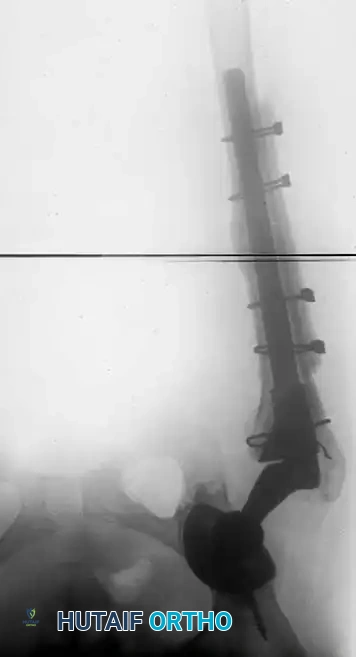

Associated Surgical & Radiographic Imaging